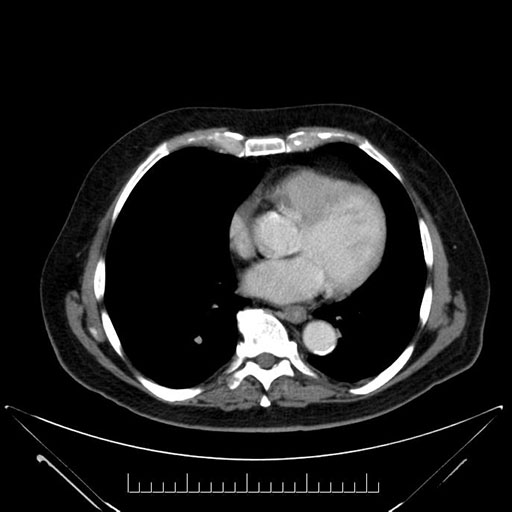

Whipple (pancreaticoduodenectomy) [case 7]

Imaging Analysis

Look through the patient's CT scan to identify any areas of concern for the necessary procedure.

Based on your CT findings, which issue(s) would give reason for "planned slowing down moment(s)" in this case?

Considering a standard Whipple procedure, what step(s) of the operation would you do differently in this case?